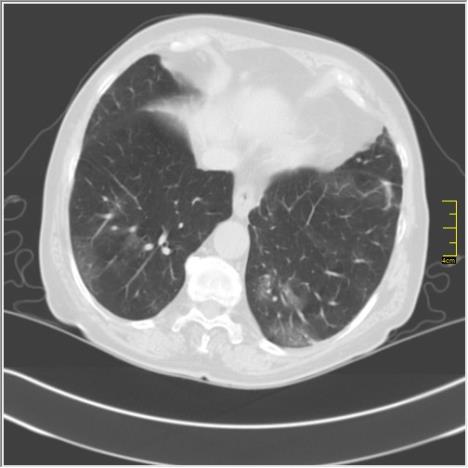

- Kod pacijenata sa "ivermektinom" postoje svi elementi kovida sa izraženom fibrozom, znači nema ni govora da neće biti komplikacija. Svi pacijenti koji koriste "ivermektin", po pravilu, nisu vakcinisani. U ovoj pandemiji je primećeno da oponenti vakcinacije pristaju na korišćenje svega drugog, pa čak i lekova za ovce, ali vakcine ne žele - napisao je dr Ivković.